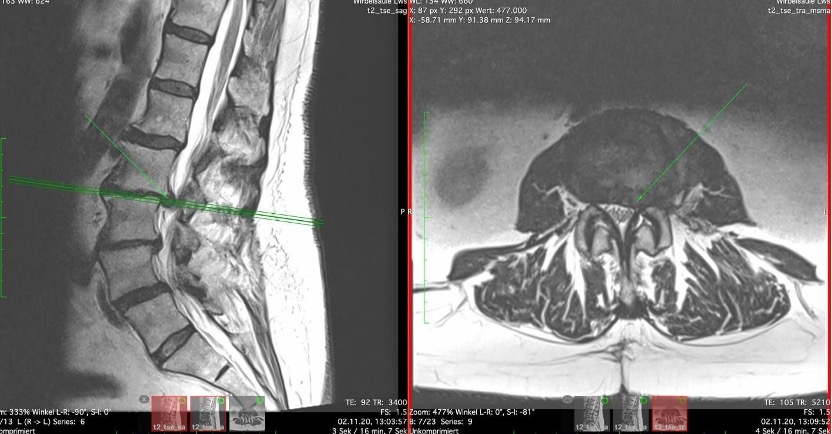

Vasilios pictures